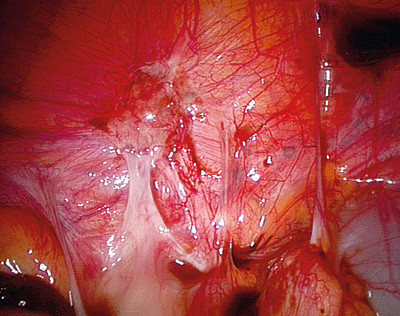

Det er veletablert praksis at peritoneal endometriose behandles kirurgisk i samme seanse som man utfører diagnostisk laparoskopi (fig 1, fig 2). Laparoskopisk teknikk vil foretrekkes av de aller fleste fremfor laparotomi ved alle former for endometriose.

Smerter assosiert med endometriose er ikke alltid relatert til sykdommens utbredelse. Det er ulike teorier for smertemekanismene ved endometriose. Aktive endometrioseimplantater kan produsere humorale faktorer som vekstfaktorer og cytokiner, implantatene kan forårsake smerter på grunn av blødning (fig 2), og de kan irritere og infiltrere nerver i bekkenet. Alle disse mulige mekanismene kan føre til bekkensmerter (9, 10).

Diagnostisk laparoskopi er gullstandarden for identifisering av peritoneal endometriose. Påvisning av implantater bør dokumenteres adekvat, fortrinnsvis bildediagnostisk, eventuelt med biopsi og histologisk verifisering av implantatene. Det er viktig at hele bukhulen inspiseres grundig, da implantatene kan ha mange ulike lokalisasjoner, også i øvre del av abdominalhulen. Operativ laparoskopi ved peritoneal endometriose innebærer reseksjon eller destruksjon av alle påviste endometrioseimplantater. Det kliniske resultatet etter laparoskopisk kirurgi ved peritoneal endometriose synes mer avhengig av operatørens dyktighet og erfaring enn av operasjonsteknikk og valg av energikilde.